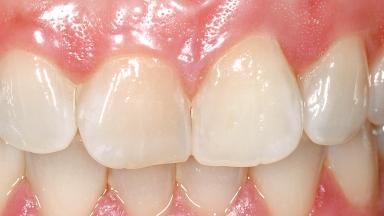

Immediate Flapless Placement of an Implant in a Maxillary Left Central Incisor Site

A 29-year-old female patient presented for treatment to replace the upper left central incisor tooth with an implant- supported restoration. The tooth had been intermittently symptomatic for the previous 12 months. The tooth had originally suffered trauma about 15 years previously. Several endodontic treatments had been performed, including an apicectomy procedure to retain the tooth. The patient was healthy and a non-smoker. She had reasonable expectations in regard to esthetic outcomes and the risk of marginal tissue recession following treatment. At medium smile, the gingival margins of the upper teeth were visible, with a display of 3 to 4 mm of the gingival margins. Gingival recession of tooth 21 and a discrepancy in the gingival levels between teeth 11 and 21 was observable during normal speech and smile.

Abutment Type Customized

Prosthesis Type FDP

Soft Tissue Contour and Volume Slightly compromised